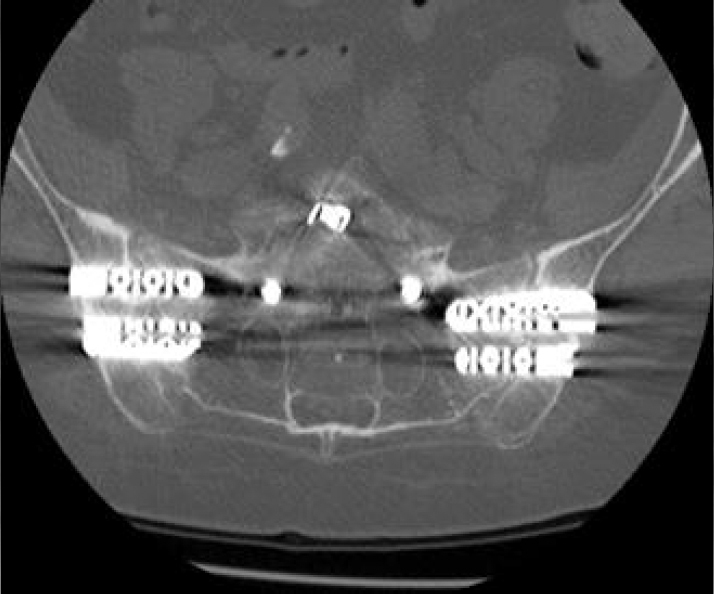

- Bilateral SI joint fusion using the iFuse 3D™ Implant System, August 2020

- CT of lumbar spine at +2 years post-op shows confirmation of the SI joint fusion.

Inline dennis 02